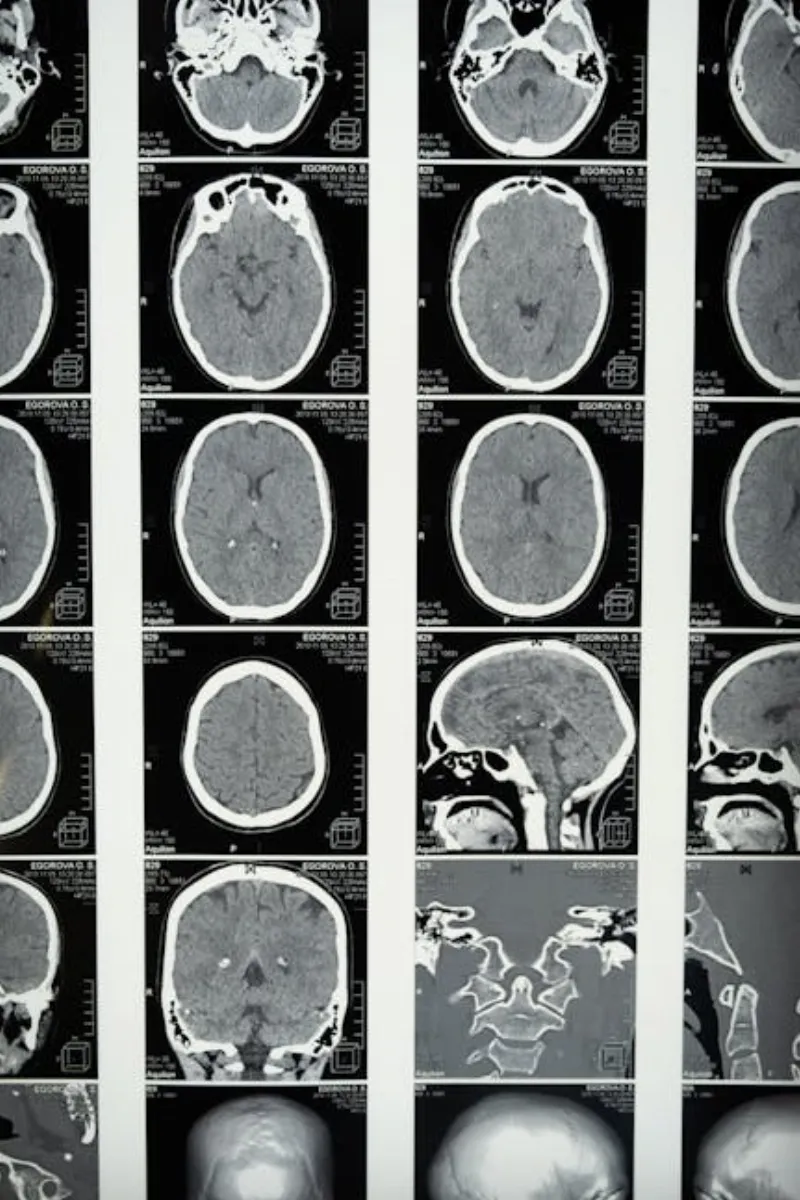

Nature Communications dergisinde yayımlanan bir çalışmaya göre, beyin taramaları, uyku başlangıç aşamalarında aktivite seviyelerinin yükseldiğini gösteriyor. Aslında, duyguları ve anıları işleyen beyin bölgeleri, uyurken daha da aktif hale gelebiliyor. Sanki beynimiz fazla mesai yapıyor, günün deneyimlerini sıralıyor ve bizi yarına hazırlıyor.